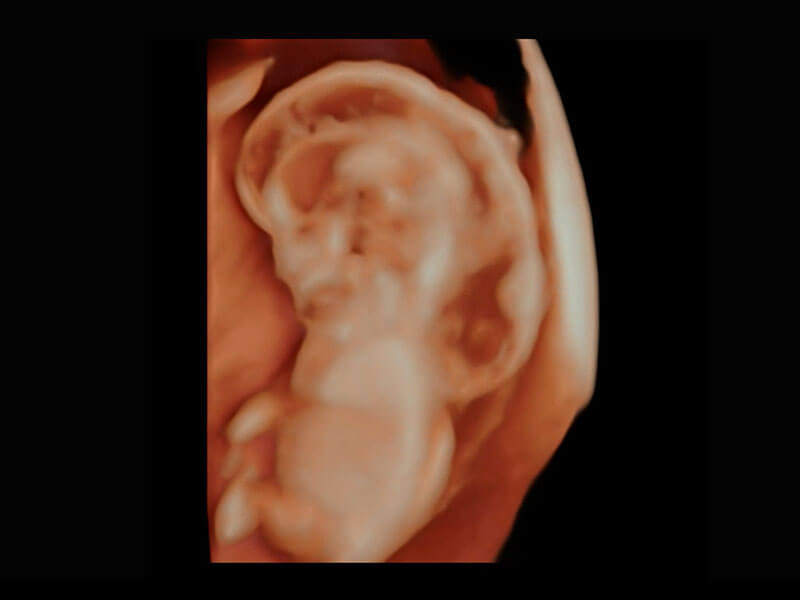

P60在胎儿早孕期超声筛查中为您带来优异的图像质量。

早孕-胎心

高分辨率容积成像-早孕胎儿

胎儿体循环

光影成像-孕囊